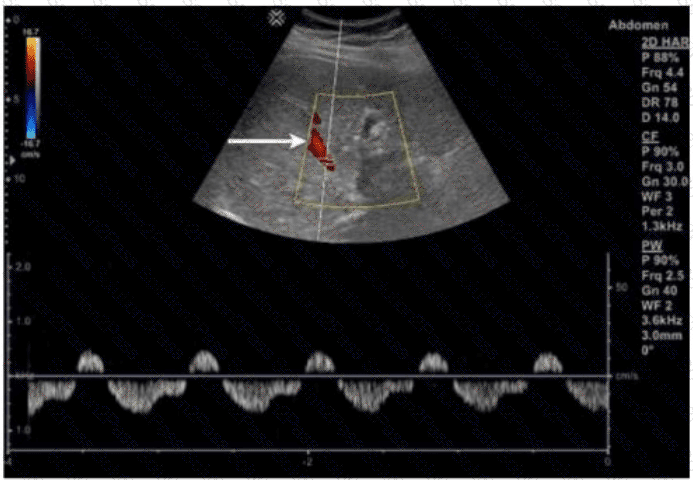

Which congenital disorder is most consistent with the finding identified by the arrow on this image?

Which structure is indicated by the arrow on this image?